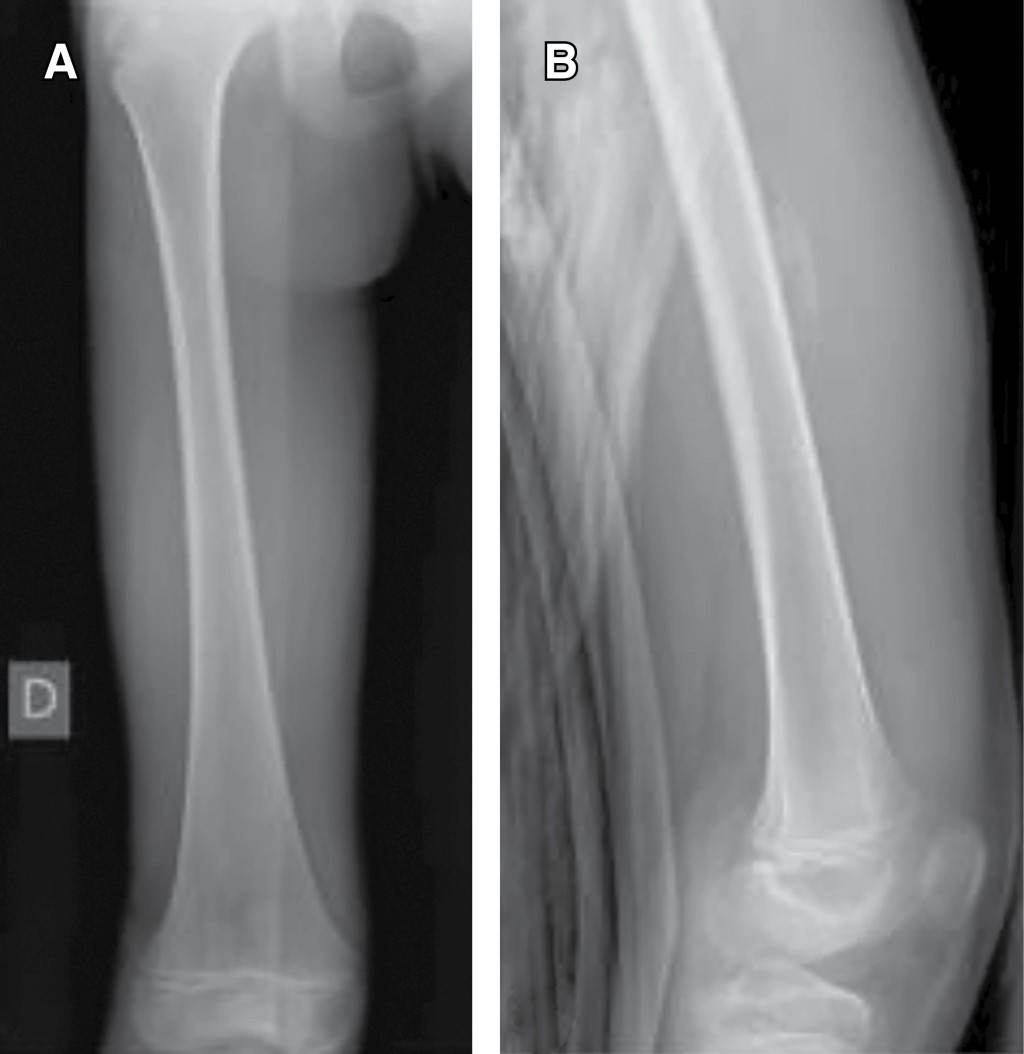

Myositis ossificans in children: a case series and literature review

Introduction: myositis ossificans (MO) is described as a non-neoplasic heterotopic bone formation at soft tissues and muscle. It is a rare entity in children, but it must be included within the differential diagnosis of a malignant tumor or an infection. Material and methods: the objective of this retrospective study is to describe three clinical cases of circumscribed myositis ossificans; the first one is a 10-year-old girl with a post-traumatic cervical injury, the second one is an 11-year-old boy with an atraumatic-type distal thigh injury, and the third one is an 8-year-old boy with a post-traumatic right thigh tumor. Results: the diagnosis was made on the basis of the clinical presentation, radiologic imaging and histopathological findings. The results obtained by conservative treatment were good in all cases, with resolution of pain and progressive reduction in size of lesions, without registering complications during follow-up. Conclusion: myositis ossificans is a rare entity, whose diagnosis is usually complex and may require a multidisciplinary team, and whose prognosis is nevertheless favorable.

Figure 1

Figure 2